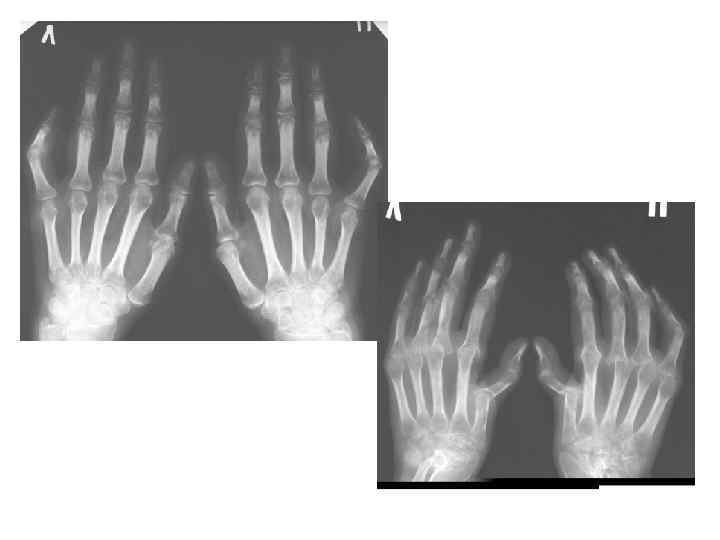

КЛАССИФИКАЦИЯ РА (3) Рентгенологическая стадия (по Штейнброкеру) • I – околосуставной остеопороз • II- остеопороз + сужение суставной щели (могут быть единичные узуры) • III – то же + множественные узуры • IV – то же + костные анкилозы

Общая рентгенологическая картина • Повреждение хряща (сужение суставной щели) • Костная эрозия

РА: тяжелое течение • Ульнарная девиация метакарпофалангеальных суставов • Радиальная девиация карпальных костей • Деформация в виде «лебединой шеи» • Деформация в виде «бутоньерки» • Экстраартикулярные проявления (ревматоидные узелки, васкулиты) Системное воспаление распространяется на суставы и околосуставные мягкие ткани. Несостоятельность связочного аппарата приводит к возникновению подвывихов суставов (Brook & Corbett, 1977; Kaarela & Kautiainen, 1997) Радиальная карпальная девиация и ульнарная девиация пальцев